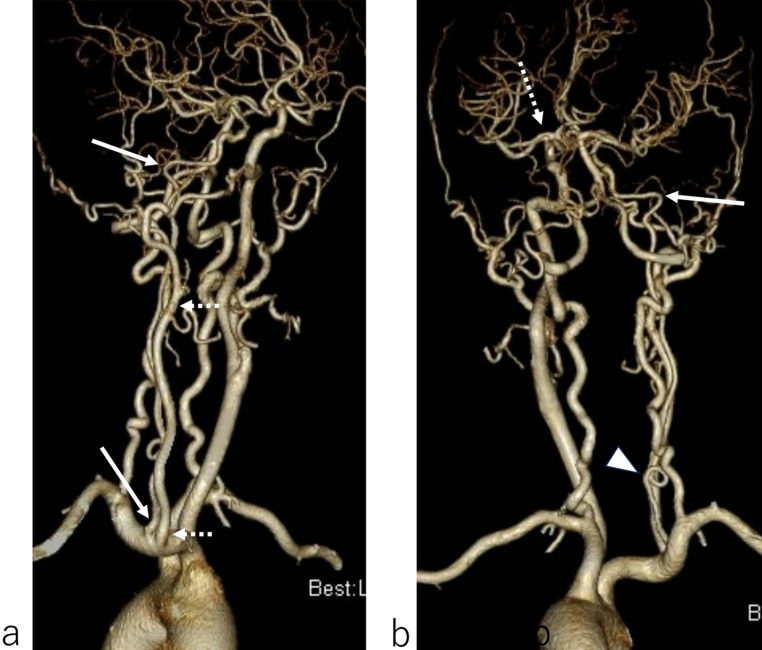

Purpose: To describe a case involving congenital absence of the right common carotid artery (CCA) associated with a left accessory middle cerebral artery (MCA) that was diagnosed by computed tomography angiography (CTA).

Methods: A 63-year-old woman with a narrow right internal carotid artery (ICA) incidentally detected on magnetic resonance imaging underwent CTA for further vascular evaluation.

Results: CTA revealed absence of the right CCA, with the right external carotid artery (ECA) branching from the brachiocephalic trunk and the right ICA branching from the right subclavian artery. The ICA was hypoplastic. A left accessory MCA was also observed. Although blood flow in the right ICA was decreased, the patient was asymptomatic; thus, conservative treatment was administered, and her clinical course remained uneventful.

Conclusion: Absence of the CCA is associated with the development of the aorta and various vascular variations; however, to our knowledge, this is the first report of an association with a contralateral accessory MCA, the existence of which may be considered incidental. Preoperative knowledge of this rare variation is important when considering endovascular treatment of cerebral aneurysms and other arterial lesions.